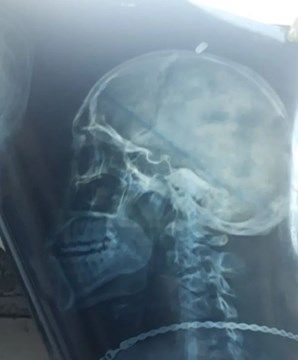

Había pasado cerca de un año, tras del supuesto piedrazo que sacudió la jornada del joven y más adelante su vida. Un médico que si hizo su trabajo completo, ordenó las radiografías para determinar por qué tanto dolor de cabeza. Lo descubrió de inmediato.

La respuesta fue todo un impacto. Le dijeron que una bala estaba alojada en su cabeza y le mostraron los análisis en los que claramente se observaba el proyectil.

“Hicieron un corte en mi cabeza y sacaron la bala. Los médicos no podían creer que sobreviví todo este tiempo con un proyectil alojado en mi cabeza. Se quedaron desconcertados cuando les conté que solo sufrí dolores de cabeza y que en ningún momento perdí la conciencia”, relató el joven.

Foto: Gentileza Crónica